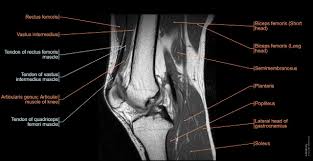

MRI (자기공명영상): 연골 및 연부 조직 손상을 확인하는 가장 정확한 방법